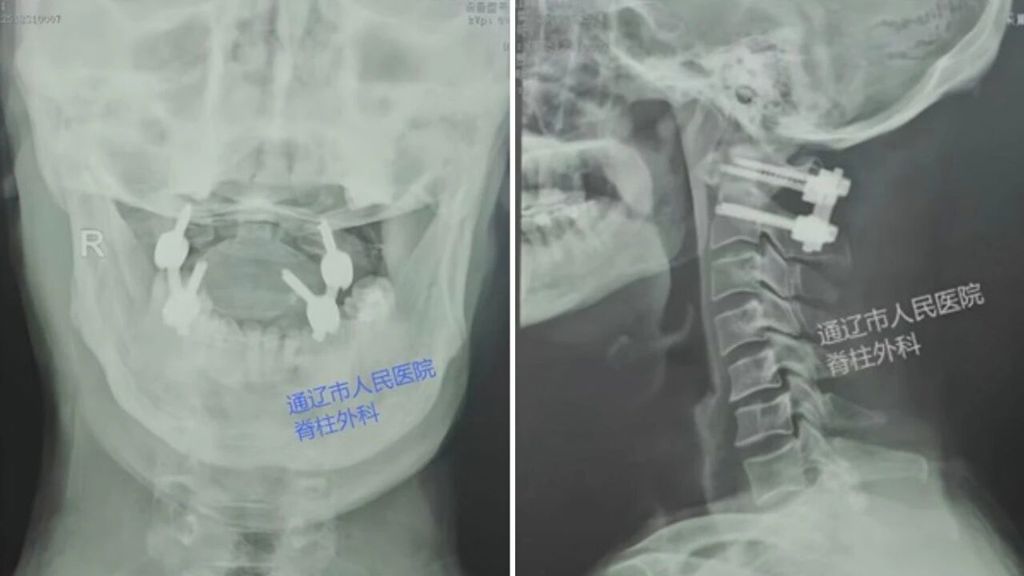

患者为57岁男性,因重物砸伤头颈部入院,伤后即出现颈部剧烈疼痛,颈部活动明显受限。完善影像学检查后,明确诊断为寰椎前后弓爆裂性骨折伴明显移位(Levine V型骨折)。该类型骨折稳定性极差、手术风险极高,患者经保守治疗后症状无明显改善,且存在潜在神经及血管损伤风险,需进一步手术干预。

针对此高危复杂病例,脊柱外科主任房芳团队对患者病情开展系统评估,结合国内外权威诊疗指南及专家共识,判定单纯保守治疗无法满足颈椎稳定性重建及功能恢复需求。经全面评估患者影像资料、神经功能及全身状况,团队一致确定手术方案:实施寰枢椎后路内固定融合手术,重建上颈椎稳定性,降低远期并发症风险。

寰枢椎区域解剖结构复杂,此类手术风险等级高,对术者临床经验、术中精准判断及麻醉全程管理均提出严苛要求。在手术麻醉科密切配合、全程护航下,脊柱外科团队严格遵循术前规划,精准完成体位摆放、精准定位及内固定植入,手术过程顺利,内固定位置精准,寰枢椎稳定性恢复良好,术中未发生神经、血管相关并发症。